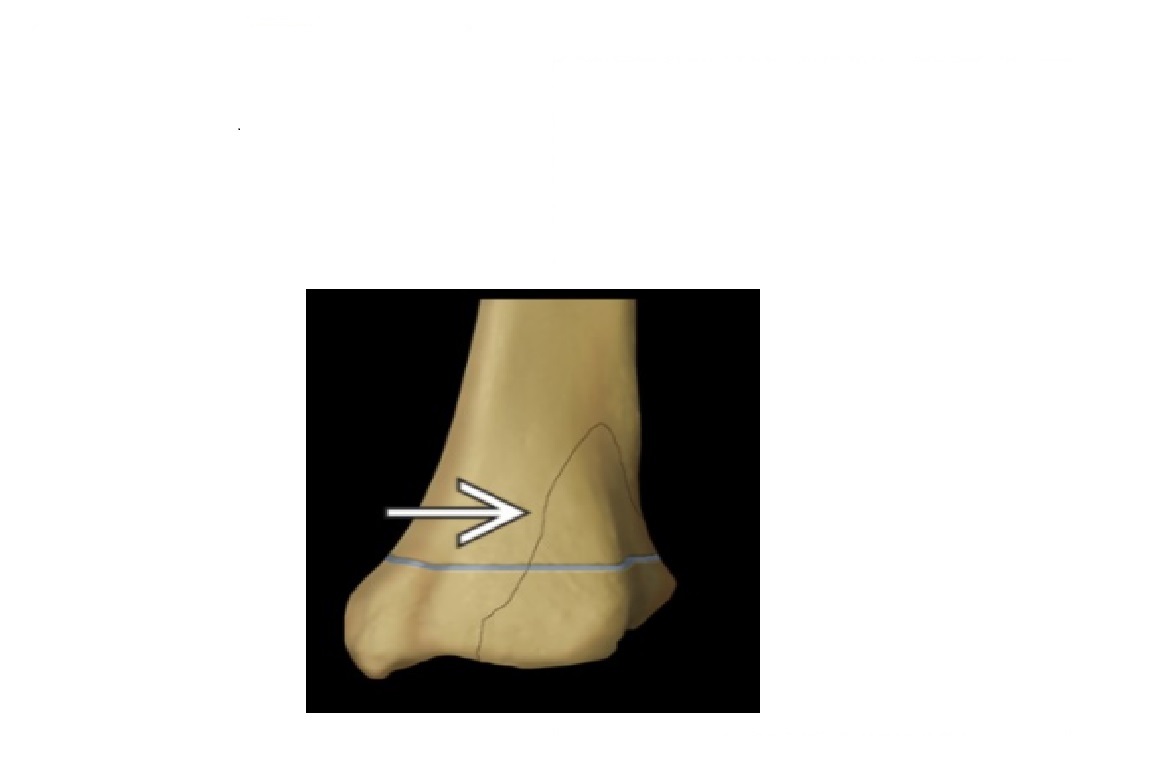

Triplane fracture

Salter-harris 4 =Vertical component through the epiphysis , horizontal component through the physis , oblique through metaphysis